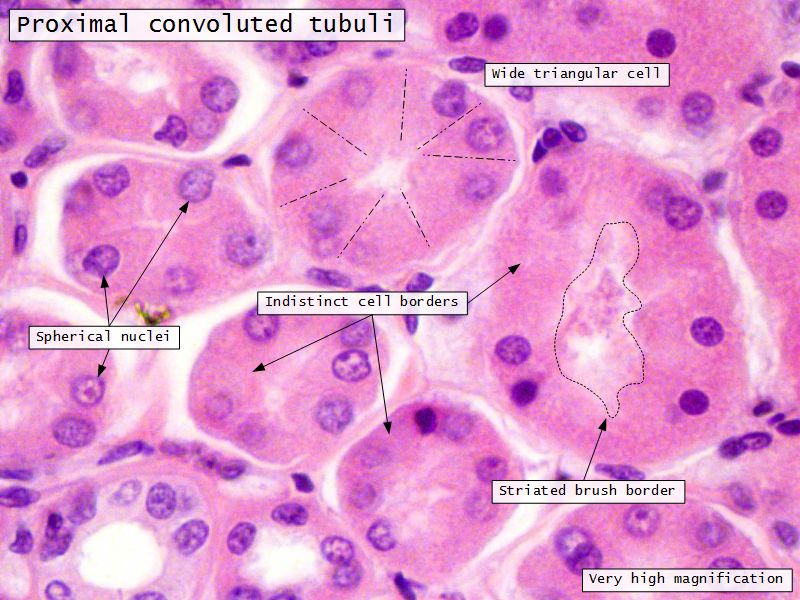

Proximal convoluted segment

- Longest part of nephron

- Wide triangular cell

- Spherical nucleus

- Indistinct cell borders

- Luminal surface

- Striated brush border